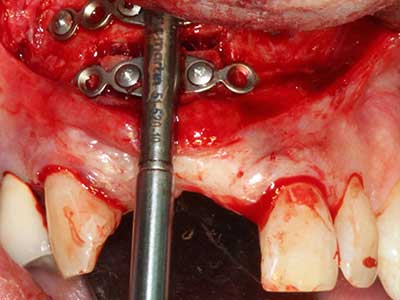

Indication: Bone splitting

Bone tissue is not simply a mineral structure but also contains a substantial proportion of collagen fibres. This means it not only has good compressive strength but also a degree of flexibility, which can be taken advantage of when performing bone augmentations. In the classical expansion procedure using bone splitting, the atrophied alveolar ridge is split longitudinally and carefully expanded after reaching an adequate osteotomy depth (Fig. 13-16), ideally without substantial removal of the periosteum (Brugnami, Caiazzo et al. 2014, Stricker, Fleiner et al. 2014). Screw and plate systems with increasing expansion distance have proven effective in separating the two bone lamellae while remaining below the fracture threshold. In general, residual bone widths of at least 3–4 mm are required (Chiapasco, Zaniboni et al. 2006) to guarantee adequate flexibility and sufficient bone coverage of the future implants. If necessary, a vertical relief osteotomy on one or both sides can improve flexibility. A combination with additional augmentation techniques, particularly on the buccal side, has been described as an alternative to the classical technique.

The splitting procedure is particularly atraumatic and there is no significant loss of dimension when using piezosaws, and there are no significant differences between implants in split jaws and implants in an alveolar ridge without a bone deficit (Chiapasco, Zaniboni et al. 2006, Danza, Guidi et al. 2009). However, sufficient continuous irrigation is essential, particularly with locally restricted and deep splitting to prevent thermal stress in the apical osteotomy regions.